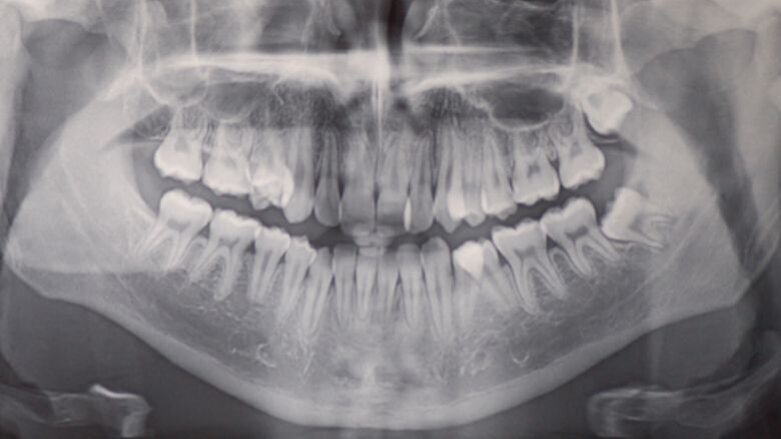

Analisi Radiografica

La radiografia panoramica (Fig. 2) mostra una sovrapposizione dentale sul primo quadrante tra 1.4 e 1.5 e sul terzo quadrante a livello coronale tra 3.4 e 3.5. I condili mandibolari sono simmetrici e non sono visibili patologie mascellari sinusali. Tutti i denti permanenti sono visibili. Vi è l’agenesia del 4.8 ed 1.8 mentre vi è la mancata eruzione del 3.8 ed 1.8. Non vi sono dilacerazioni radicolari, si nota un riassorbimento radicolare con una mancata formazione dell’apice radicolare del 4.5, 3.5. La radiografia laterale del cranio (Fig. 2) mostra le vie aeree superiori libere. L’indice di maturazione delle vertebre cervicali (CVMS) è di grado 6. L’analisi cefalometrica iniziale rivela una classe II sagittale mandibolare a causa di una mandibola retrognatica (SNPog = 72,2°), un tendenza mandibolare di iperdivergenza, ed un angolo interincisale ridotto. L’OJ e l’OB è nella norma.